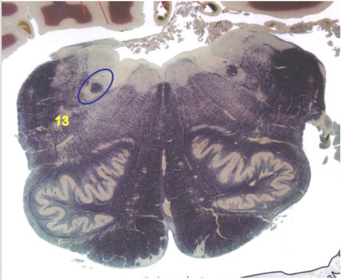

| Interposed nuclei | |

| Medial longitudinal fasciculus | |

| Facial nerve root - internal genu | |

| Abducens nucleus | |

| Lateral vestibular nucleus | |

| Superior vestibular nucleus | |

| Inferior cerebellar peduncle | |

| Superior cerebellar peduncle | |

| Dentate nucleus | |

| Fastigial nucleus | |

| Anterior spinocerebellar tract | |

| Spinal nucleus of V | |

| Spinal tract of V | |

| Middle cerebellar peduncle | |

| Medial lemniscus | |

| Trapezoid body | |

| Ventral trigeminothalamic tract | |

| Superior olive | |

| Longitudinal pontine fibers (corticospinal tract) | |

| Transverse pontine fibers (dark fibers) | |

| Pontine nuclei (pale) | |

| Central tegmental tract | |

| ALS | |

| Principle nucleus of V | |

| Mesencephalic V tract | |

| Trigeminal root fibers | |

| Motor nucleus of V | |